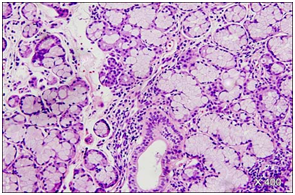

6. Positive anti SS-A or anti SS-B antibody results. Four criterions must be positive along with a positive 5 or 6 for the confirmation of Sjogren’s syndrome. Secondary Sjogren;s syndrome is designated with a coexistent potential connective tissue disorder there are manifestations of oral or ocular dryness exist with criterion 3 or 4 or 5. A tissue biopsy of a moisture producing gland (usually the minor salivary glands of the lower lip) is confirmatory (Figures 2‒5).

7. Figure 2 Minor salivary gland with acinar atrophy, lymphoid infiltrate and interstitial fibrosis.

Figure 3 Minor salivary glands with lymphocytic sialadenitis.

Sjogren’s syndrome distinctly elucidates immune mediation in the major and minor salivary glands. A focal, miniature infiltrate of T and B lymphocytes and plasma cells appears around the ducts to subsequently form germinal centers (B and T lymphocytes, plasma cells etc). The cell aggregates are monotypic as seen by immune-histochemical staining for kappa and lambda light chains (monoclonal/light chain restriction). The prevalence of non-hodgkin’s lymphoma is proportionately 44 times higher in patients with Sjogren’s syndrome than in the general population. The evolving lymphoma is established in the mucosal tissue, major salivary glands, stomach, lung, lymph node (Table 3).5